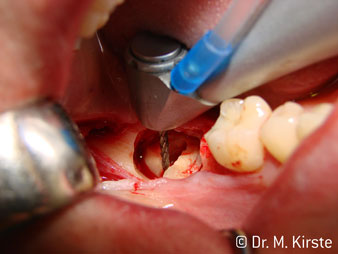

Die Winkelwahl des 45° Handstücks bringt viele Vorteile in der Anwendung. Chirurgisch tätige Kollegen, und für diese ist das Handstück in erster Linie entwickelt worden, werden schnell bemerken, dass man sehr gezielt arbeiten kann. Insbesondere bei der Weisheitszahnentfernung (Abb. 2) bedarf es keiner großen Weichteilabspreizungen im Wangenbereich (Abb. 3). Die Handstückkopfgestaltung kombiniert mit leichten Kopfdrehungen bei der Präparation lassen ein sicheres und schnelles Arbeiten im retromolaren Bereich zu.

Die professionelle Lagergestaltung im Innenleben des Handstückkopfes garantiert einen ruhigen Lauf der Bohrer, bei der Zahn- oder Wurzelseparation (Abb. 4 - 9) zeigt sich ein beeindruckendes Schnittbild ohne Schlageffekte.

Abb. 5

Abb. 7

Abb. 9

Abb. 4

Abb. 6

Abb. 8